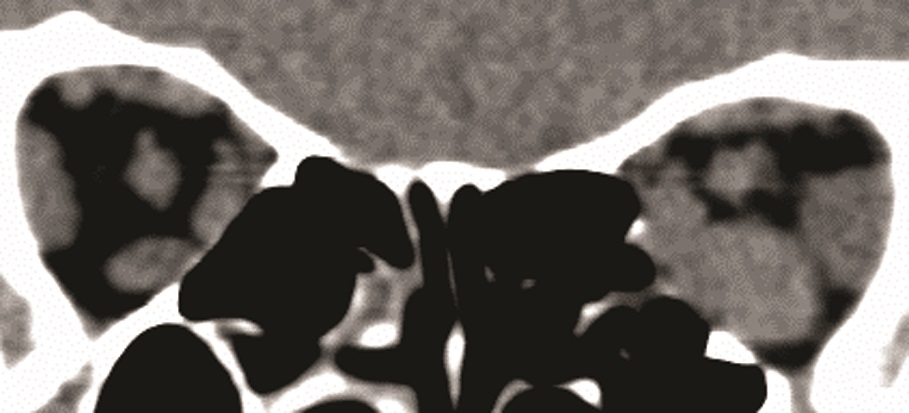

13. Fig. 8. Clinical manifestations of endocrine ophthalmopathy with optic neuropathy. b - MSCT of the orbits, coronal projection - compression of the optic nerve (white arrows) at the apex of the orbit increased in volume of the EOM. | |

| Subject | ||

| Type | Other | |

View

(596KB)

|

Indexing metadata ▾ | |